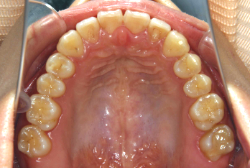

診断の結果、典型的なアングル2級1類の上顎前突です。上下歯列の正中の不一致も見られます。しかし、歯の大きさは平均値に近く、配列の凸凹がそれほど見られません。このまま放置すると、将来的には抜歯を伴う矯正治療を行う可能性が高くなりますが、このタイミングで適切な治療をすると、非抜歯治療が可能かもしれません。

矯正歯科医が着目するのは、奥歯の噛み合わせの位置関係です。前歯の位置にそれなりの差が生じていても、奥歯の位置が正しければそれほど重症という評価にはなりません。このケースの場合は、上下の第一大臼歯の位置関係は、直線的に一致しているタイプでした(矢印が一致)。混合歯列時期の奥歯の位置関係としては、ほぼ正常な状態といえますが、症状から言うと、上の奥歯をもっと後ろに下げてやることができれば、上顎歯列全体に余裕ができるので、凸凹も解消できるし、前歯の傾きを内向きに修正することもできると考えられました。しかしこのまま全体に永久歯が生えきってしまうと、上の前歯が出たままになってしまいますので、生え替わりが完了する前に大急ぎで奥歯を後ろに下げる必要があると判断しました。

ネックバンドを1年半使用して、上顎大臼歯が十分後ろに下がったところで、裏側にリンガルアーチという固定のワイヤーを取り付けて、新しく生じた隙間が狭くならないよう「保隙(ほげき)」という処置をして、永久歯が生えそろうまで待機中の様子です。配列全体に隙間が生じているのがお分かりいただけると思います。これだけの隙間が確保できていれば、抜歯をしなくても、あとで上の前歯を内側に理想的な角度で引っ込めることができます。このように完全に永久歯列になる前に、十分な隙間が確保できるかどうかが、非抜歯で矯正できるかどうかの分かれ目になります。